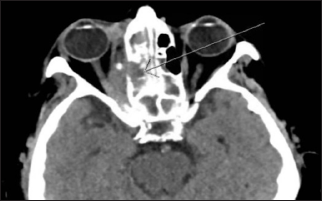

The patient was readmitted 2 weeks later for lower extremity deep vein thrombosis in the setting of a thrombocytopenia of 65000 and a persistent medial orbital mass. A new antibiotic regimen of doxycycline/metronidazole resulted in resolution of the thrombocytopenia. Antibiotics were later discontinued all together due to lack of ocular improvement. The patient was taken back to the operating room for a repeat biopsy due to a CT scan showing an enhancing mass involving the extraconal soft tissue paralleling the posterior ethmoid air cells, concerning for a possible neoplasm. Intra operatively, the medial rectus appeared to be grayish in color concerning for muscle infarction. Final pathology noted a partial fibro vascular and fibro muscular necrosis containing only a few crushed lymphocytes and scattered acute inflammatory cells. Cultures continued to be negative. Flow cytometry was negative for lymphoma. No diagnostic evidence of malignancy or features of lymph proliferative disorder were indicated on histology. CT chest/ abdomen/pelvis to rule out metastatic malignancy was only notable for a 1 cm pulmonary nodule in left lower lobe. Idiopathic orbital inflammatory syndrome labs showed mildly elevated erythrocyte sedimentation rate and CRP; negative RPR, ANA, c-ANCA and p-ANCA. Given these findings, the diagnosis of chronic sinusitis with orbital extension was still the leading diagnosis. The patient was discharged again on a steroid taper (Figures 2 & 3).

Figure 2: Retrobulbar extraconal mass along the medial orbit near the apex impinging on the right optic nerve, and consolidation in the ethmoid air cells and the sphenoid sinus

Figure 3: Persistent opacification of sphenoid sinuses, right ethmoidal air cells with extension from medial orbit into the orbial apex (arrow). New involvement of maxiallary and possible frontal sinuses